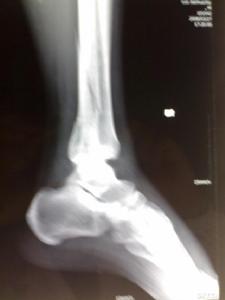

跟骨骨折影像病人有典型的外傷史,患足承重困難和足跟疼痛,局部觸痛、腫脹和皮下淤血斑亦多明顯。在較嚴重的壓縮骨折時,除可見到足後跟的高度變低和足跟橫徑變寬以及外踝下部正常凹陷消失外,距下關節話動亦完全喪失。但跟骨周邊骨折僅有局部腫脹及壓痛,而距下關節活動範圍多屬正常。x線正、側、軸位片可明確跟骨的結節關節角和其橫徑寬度的改變。

影像學表現

(1)跟骨前突骨折。

(2)跟骨結節的垂直骨折。

(3)載距突骨折。

(4)跟骨壓縮性骨折。

(5)跟骨粉碎性骨折。